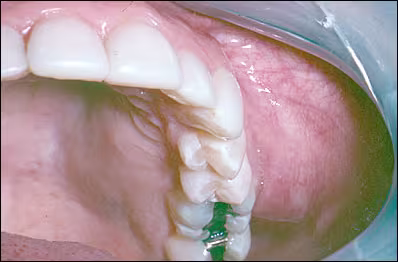

Extraoral examination showed mild facial asymmetry with subtle swelling of the left zygomatic region. Intraorally a prominent bony-hard, non-tender expansion of the left zygoma and maxillary alveolar process was evident measuring approximately 3 x 4 cm. There was no associated color change or ulceration. In addition a mild degree of bony expansion of the left posterior hard palate was noted. (Figure 1)

Figure 1. Expansile mass involving the left maxillary vestibule.